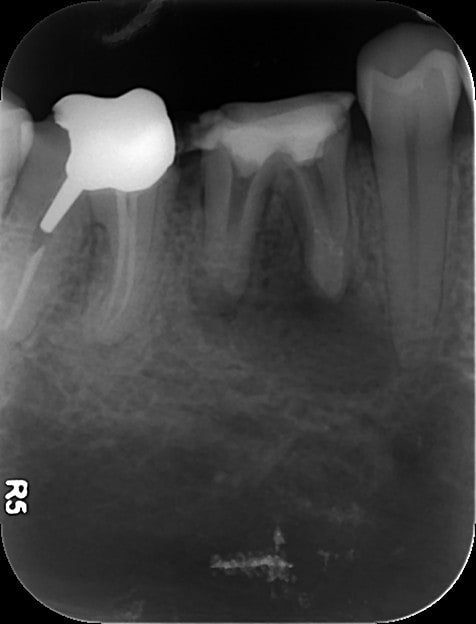

Premier cas aujourd'hui avec Smartseal et les cones qui vont avec... 14 super calcifiée, 2h30 plus tard :

Endo 49  1  preop t5er2c - Eugenol

Endo 49  2  end rdggnk - Eugenol